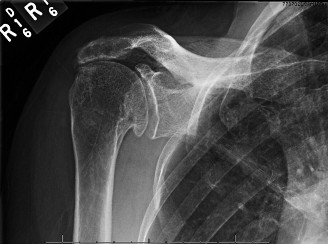

A 47-year-old, right-hand-dominant male presents to your clinic complaining of right shoulder weakness for th…